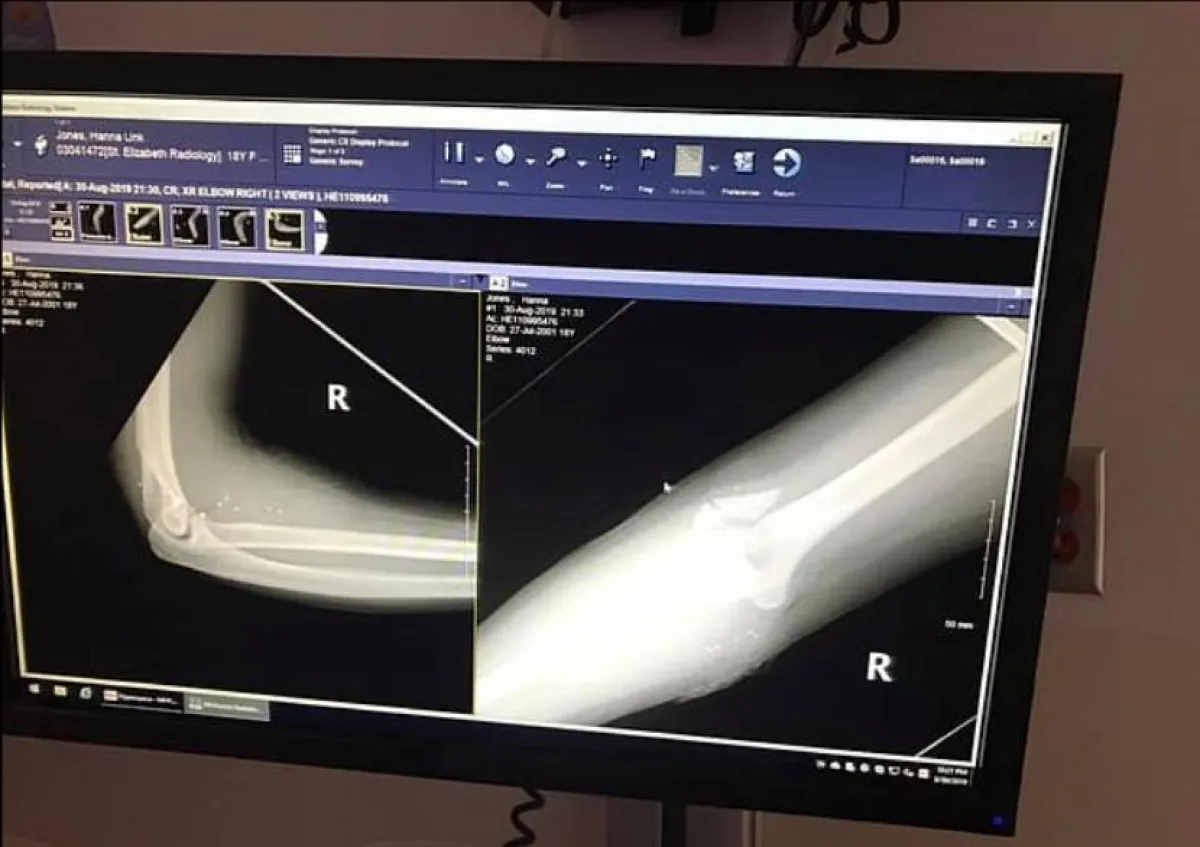

وتابع رئيس الشرطة المحلية، أنه لحسن الحظ، أن الشابة الآن بخير رغم أن الرصاصة تسببت لها بـ3 كسور في كوعها، لكنها تلقت العلاج اللازم في مستشفى سانت إليزابيث يونجستاون فور نقلها إلى هناك. وأضاف أن مركز الشرطة قدم تقريره للنائب العام بتفاصيل الحادثة، بانتظار إصدار حكم في هذه القضية.